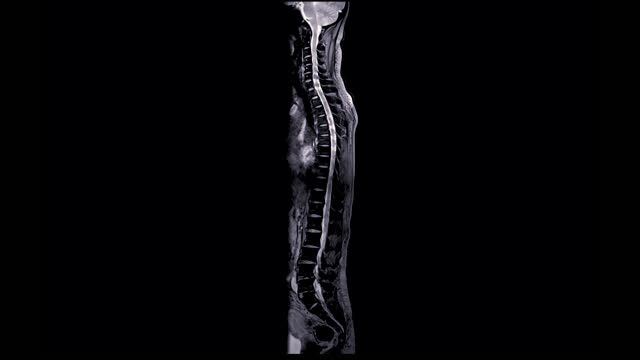

척추관협착증에 대한 이해

척추관협착증은 척추 주변의 근육과 인대가 퇴행하여 척추관 내 황색 인대가 비정상적으로 부풀어 오르면서 발생하는 퇴행성 척추질환 중 하나입니다. 이 질환은 가까운 거리도 통증으로 인해 걷기가 어려워지는 특징을 가지고 있으며, 새벽에 다리에 통증을 느끼는 경우가 많습니다.